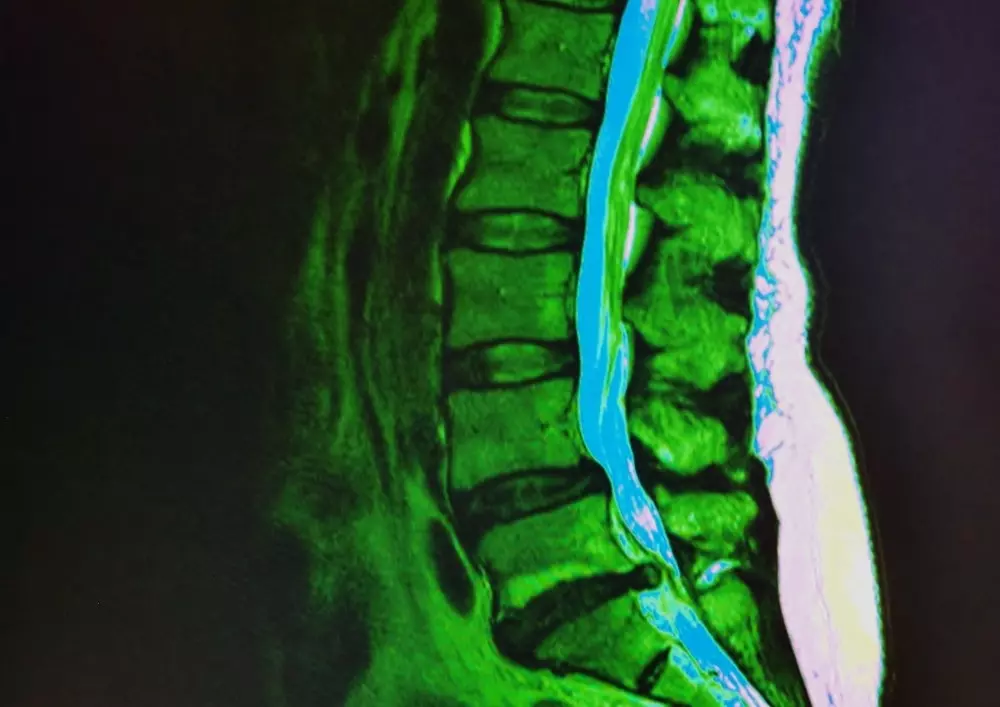

Ponadto zapraszamy do zapoznania się z opracowaniem pt. „Diagnostyka różnicowa odcinka lędźwiowego kręgosłupa i stawu krzyżowo-biodrowego – część 2”. Jest to kontynuacja artykułu z poprzedniego numeru, dlatego gorąco zachęcamy do sięgnięcia po jego pierwszą częścią.